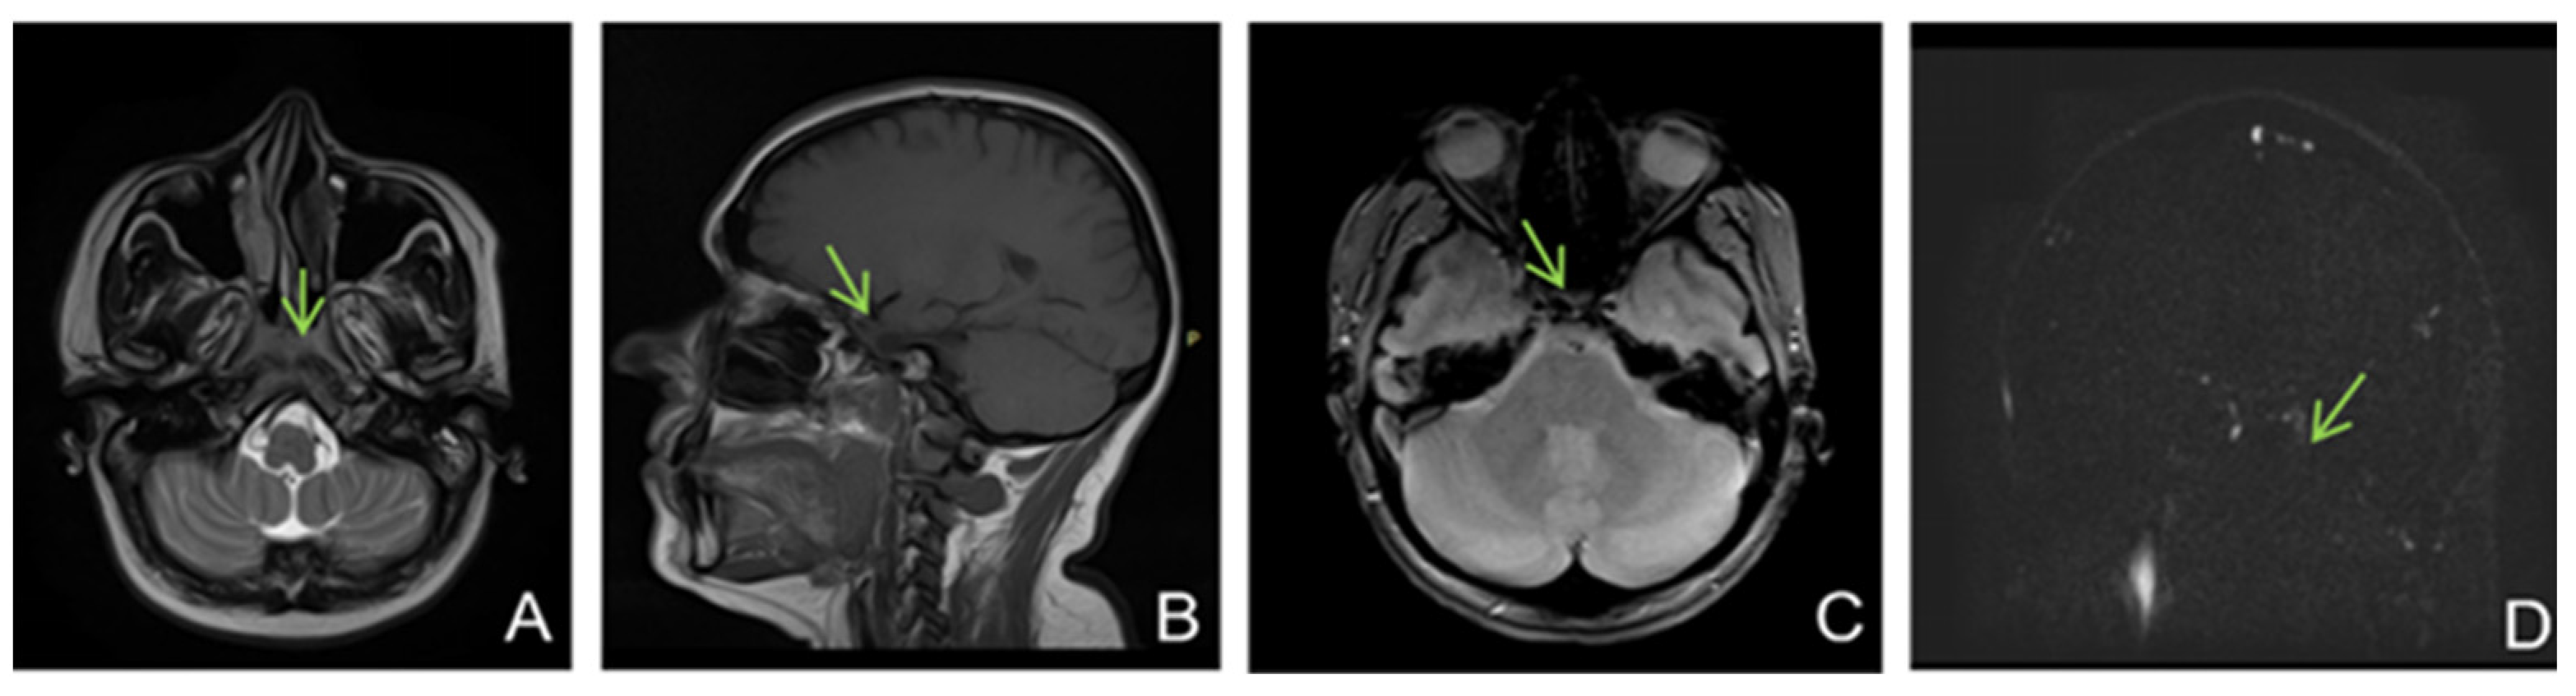

We decided to have an emergency MRI, but considering that the patient was pregnant, contrast was not used.

MRI showed (Figure 6) changes evoking venous thrombosis of left transverse and sigmoid sinuses, straight sinus, vein of Galen, internal cerebral and basal veins with extensive venous infarcts at the level of bilateral basal ganglia and a left temporo-occipital subcortical area.

Figure 6.

MRI without contrast enhancement ((A)—T2 axial, (B)—FLAIR coronal, (C)—DWI axial, (D)—ADC axial, (E)—venous TOF sagittal) shows hyperintensities of the thalamic nuclei on T2, FLAIR and DWI, with areas of restricted diffusion included and no flow in Galen’s vein, internal cerebral veins, straight sinus, and inferior sagittal sinus.

She was admitted to the intensive care unit for continuous monitoring and started receiving anticoagulant and supportive treatment represented by continuous intravenous unfractionated heparin with flow adapted to the APTT value, isotonic fluids, vitamin therapy, physical therapy, pneumatic compression, and empiric antiviral therapy until encephalitis was excluded.

On the first day after admission, the patient′s clinical condition deteriorated. She became febrile, presented episodes of drowsiness alternating with spontaneous wakefulness and psychomotor agitation, involuntary hyperextension movements at the thoracic level, bilateral grasping, and plantar clonus bilaterally, and she was only reacting to nociceptive stimuli. The ophthalmological examination ruled out papilledema. A lumbar puncture was performed, and the result was negative for bacteria and viruses. The thrombophilia profile tests were requested and were found to be positive for: homozygous V H129 R mutation, heterozygous PAI1 4G/5G, and homozygous MTHFR A 1289C mutation.

In the following days, the patient′s condition continued to worsen. She did not respond to nociceptive stimuli, spontaneously mobilized her limbs, and had involuntary movements of the jaw. Considering the unfavorable and unpredictable evolution, in agreement with the family, we decided to perform therapeutic abortion. A new brain CT was performed (Figure 7).